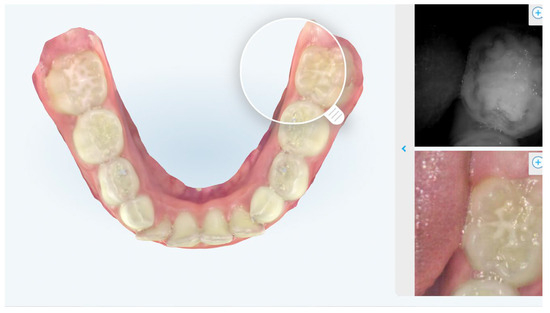

Figure 2.

Intraoral scan shows sealants on 3.6.

In the population taken into consideration in this study, children between 6 and 12 years old who underwent the intraoral scan and who participated in the completing the questionnaire at the Department of Pediatric Dentistry of the University of L’Aquila, we found that the Italian version of the “questionnaire on the effectiveness and satisfaction of the intraoral scanner in the growing patient”, developed by a group of Italian native speakers of different disciplines, has demonstrated good internal consistency and moderate retest reliability, satisfying its validity. The relatively limited size of the study did not allow us to find statistically significant differences based on gender. In agreement with the results of the questionnaire, we can state that the scanning of the arches, through the use of intraoral scanner, has the ability to positively interfere in generating awareness in the parent about the child’s health, can interact in the trinomial dentist-child–parent communication and can be considered useful for detection of the footprint. For this last point, the results of the questionnaire confirm what already exists is present in the literature. The Italian version of the questionnaire proposed to children patients and their parents enjoys a satisfactory internal coherence index. Indeed, Cronbach’s alpha had a value of 0.728. Test–retest reliability was moderate for four questions (for Q4, Q9, Parent’s Q11 and Child’s Q1) with a score ICC between 0.5 and 0.75. The remaining questions were considered statistically insignificant, having a score less than 0.5. Regarding the reliability of the dichotomous variables, the Cohen’s kappa index stands at 81.75%; for this reason, it is considered highly reliable. Previous studies have shown how visualization and understanding the treatment helps the patient follow through the indications provided by the clinician. This mechanism is very similar to the behavioral technique Tell–Show–Do already present in the literature. From the results, in fact, we note that the visualization of the reconstruction of the model in 3D generates in the patient, rather than in the parent, a higher level of understanding (Figure 2 and Figure 3).